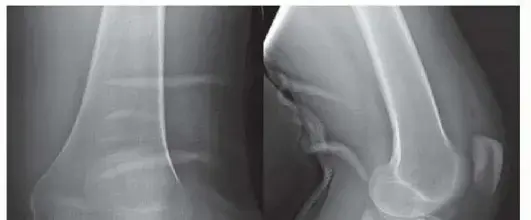

2. الأشعة السينية (X-rays): تُظهر الكسور في العظام، ولكن قد لا تكشف بوضوح عن جميع تفاصيل كسور الهضبة الخلفية المعقدة، خاصة تلك التي تكون متجهة للخلف.

3. التصوير المقطعي المحوسب (CT Scan): يُعد هذا التصوير حاسماً للغاية في تشخيص كسور الهضبة الظنبوبية الخلفية. فهو يوفر صوراً ثلاثية الأبعاد مفصلة للكسر، ويحدد حجم النزوح، وعدد الشظايا العظمية، ومدى تأثر سطح المفصل، مما يساعد الجراح على التخطيط الدقيق للعملية.